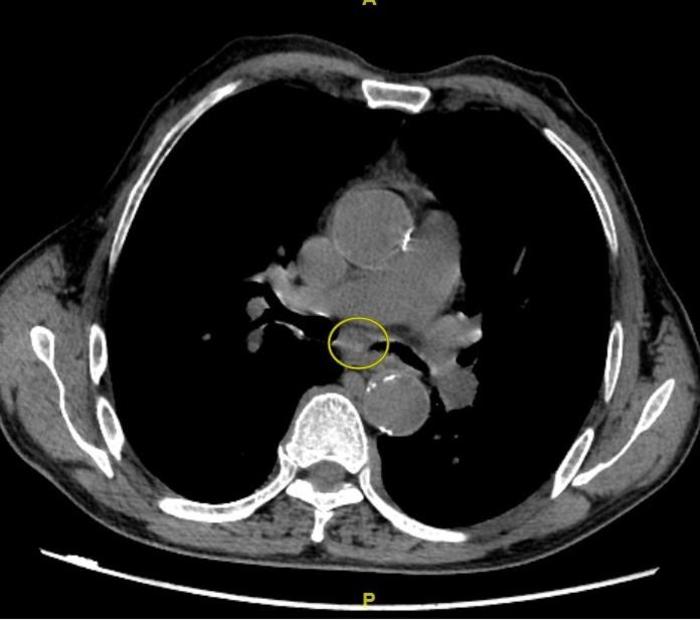

如下图,CT发现隆突下淋巴结肿大。圆圈内为隆突下淋巴结。